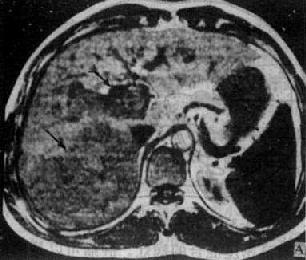

肝癌

图4-3-6 肝癌(MRI)

A、T1WI肝右叶可见大块较低信号区,其内信号不均,轮廓不规

则(↓)。门静脉内可见相同信号强度影像,为癌栓所致(↓)

B、T2WI上述稍低信号区成为稍高信号区(↓),门静脉内癌栓的信

号也增强(↓)